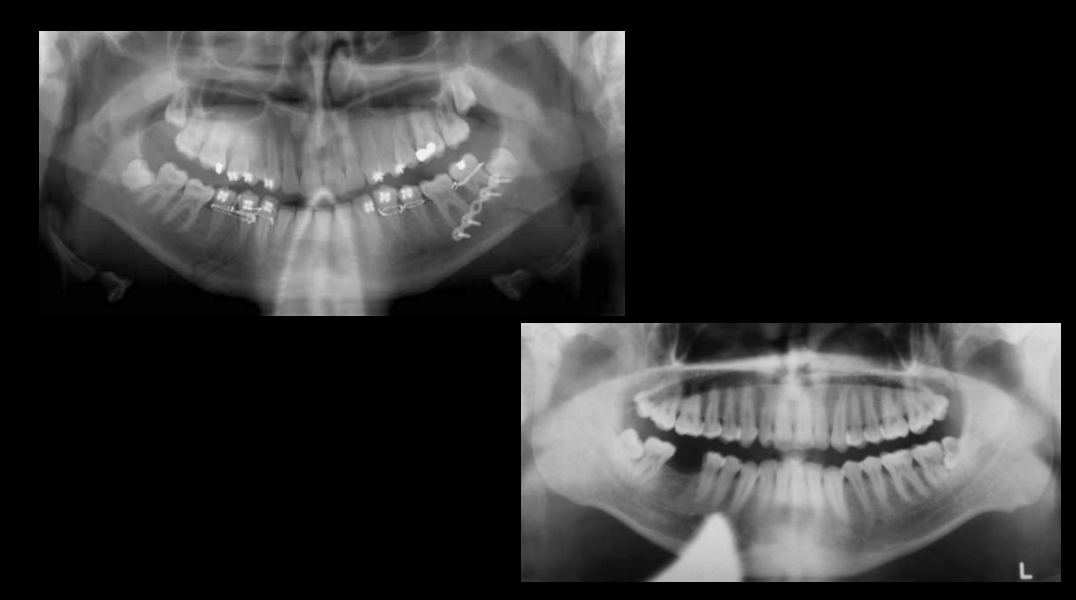

Image 1: Ghost image of a necklace/chain. Also jaw surgery.

Image 2: Lead apron

Errors in patient preparation